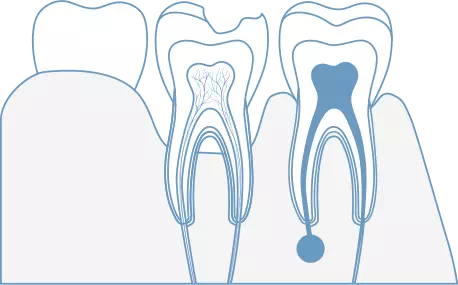

虫歯など様々な理由で歯の内部に細菌感染が広がることがあります。歯内療法(根管治療)とは、文字通り歯の内部の治療で、感染が広がった根管(神経が通る管)に対して適切な治療を行うことにより歯の機能を回復させることができます。

歯髄の侵襲レベルによって

歯の残存確率を上げる選択肢